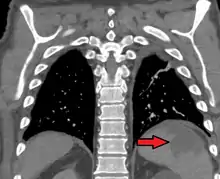

Splenic infarction

Splenic infarction is a condition in which blood flow supply to the spleen is compromised,[1] leading to partial or complete infarction (tissue death due to oxygen shortage) in the organ.[2] Splenic infarction occurs when the splenic artery or one of its branches are occluded, for example by a blood clot.[3]

| Splenic infarct seen on CT | |

An abdominal CT scan is the most commonly used modality to confirm the diagnosis,[3] although abdominal ultrasound can also contribute.[5][6][7]